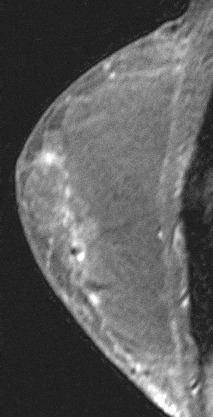

Linear enhancement can be further described as smooth, irregular or clumped (Fig. 19). As with smooth masses, smooth linear enhancement is suggestive of a benign process. Irregular enhancement refers to any non-smooth enhancement and may be continuous or discontinuous. Clumped enhancement refers to an aggregate of enhancing masses or foci that may be confluent in a cobblestone pattern (Fig. 20). Linear enhancement is suggestive of DCIS especially if clumped or irregular.

Figure 19. Clumped enhancement. Pathology – DCIS.